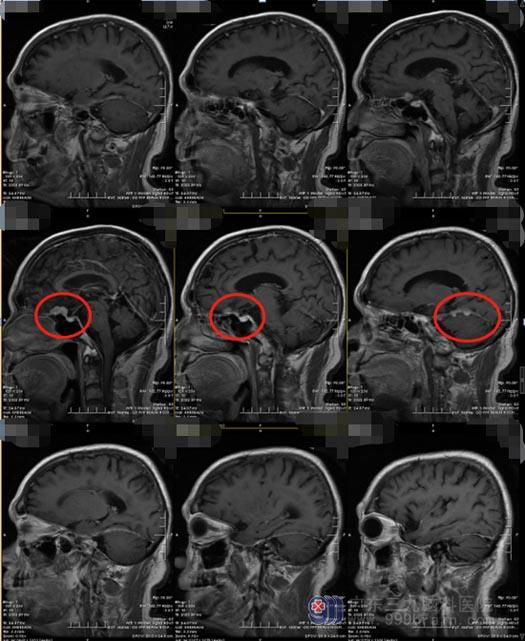

在广东三九脑科医院,医院副院长、神经外五科主任鲁明阅片后认为:患者出现鞍上占位病变,脑膜瘤可能性大,不能排除颅内动脉瘤的可能,需要行进一步的检查。头颅MRI增强扫描显示:鞍上实性占位性病变,大小约21.2mm×9mm×12.7mm,增强后明显均匀强化,诊断为脑膜瘤。